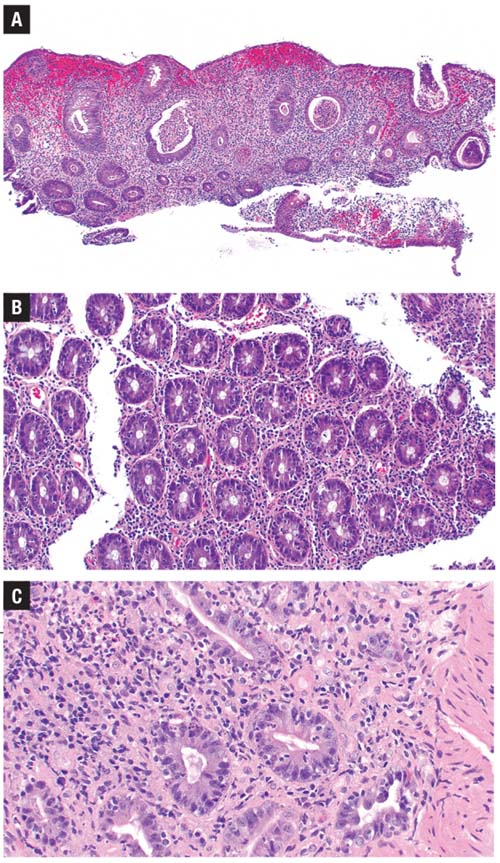

cases of PD-1 inhibitor colitis.

A) There is significant histologic overlap with inflammatory bowel disease. B) This example shows increased intraepithelial lymphocytes in addition to neutrophilic cryptitis.

C) Here, increased apoptotic

bodies are present.